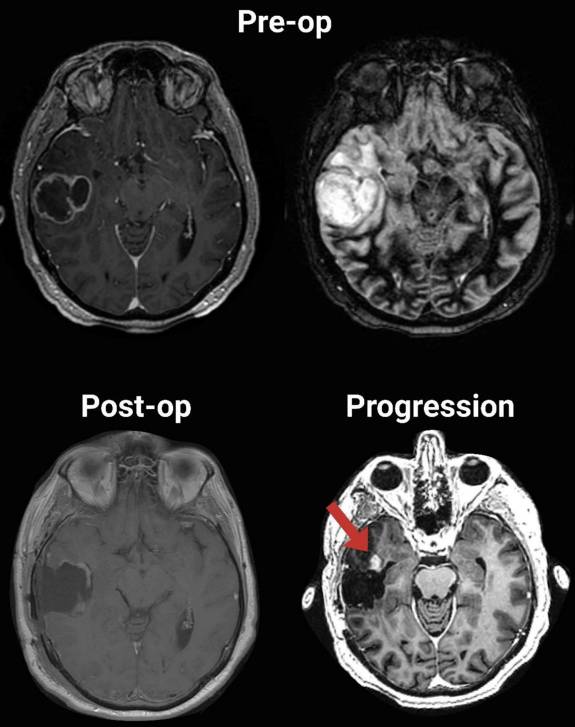

Fares et al Jawad Fares, MD showed temporal IDH-wildtype GBM often progresses anteriorly post-resection. Anterior temporal lobectomy may reduce progression in some cases. FLAIR imaging’s predictive value is limited, urging advanced techniques.#JNO Read more:link.springer.com/article/10.100…

Fares et al <a href="/DrJawadFares/">Jawad Fares, MD</a> showed temporal IDH-wildtype GBM often progresses anteriorly post-resection. Anterior temporal lobectomy may reduce progression in some cases. FLAIR imaging’s predictive value is limited, urging advanced techniques.#JNO

Read more:link.springer.com/article/10.100…